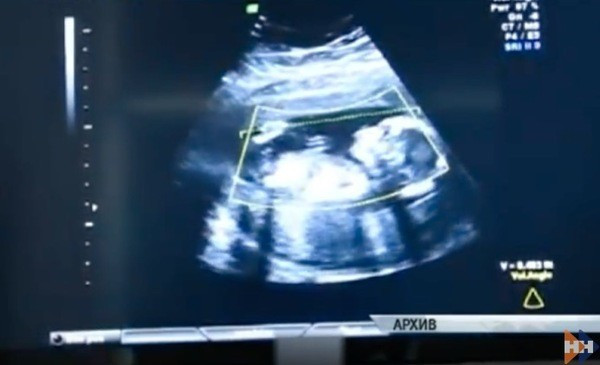

Doktorlar kadını muayene ettikten sonra herkesin şok olacağı bir tespitte bulundular. Bebek, kadının rahminde değil karın boşluğundaydı. Doktorlar, kadının dış gebeliği olduğunu anladılar. Dış gebelik, gebelik ürünü olan döllenmiş yumurtanın rahim boşluğu dışında yerleşmesiyle oluşan bir gebelik komplikasyonu.